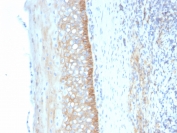

IHC staining of FFPE human tonsil tissue with CD73 antibody (clone NT5E/4679). Inset: PBS used in place of primary Ab (secondary Ab negative control). HIER: boil tissue sections in pH 9 10mM Tris with 1mM EDTA for 20 min and allow to cool before testing.

IHC staining of FFPE human tonsil tissue with CD73 antibody (clone NT5E/4679). HIER: boil tissue sections in pH 9 10mM Tris with 1mM EDTA for 20 min and allow to cool before testing.